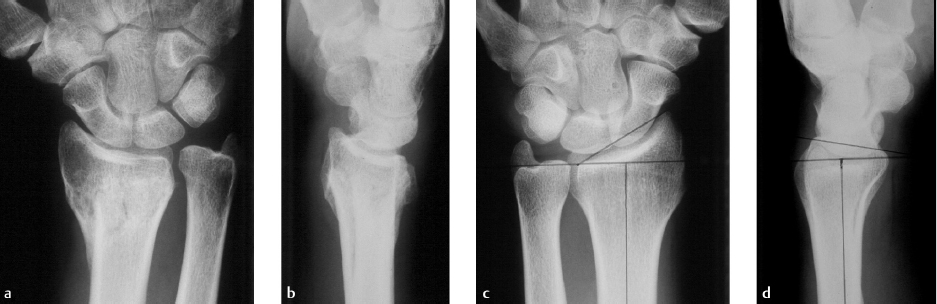

Especially when multiplanar and intra-articular deformities are present, corrective osteotomies are technically challenging procedures. Preoperative planning with comparison of the bony anatomy with the normal, contralateral side can be helpful (► Fig. 53.2). Computerized tomographic (CT) scanning can add useful information in the preoperative stage, especially in fractures with an articular component. 10

Preoperative planning is essential for intraoperative decision making. Desired angles for correction are determined corresponding to the opposite side (► Fig. 53.4). Using templated X-rays to assess length, osteotomy location, and osteotomy or either printing out X-rays and constructing osteotomies on the paper to determine appropriate cut locations, angles, and center of rotation can be very helpful (► Fig. 53.5). CT-derived threedimensional bone models can allow for preoperative planning.

Two methods for preoperative planning have been described by Nagy and Fernandez on the basis of plain X-ray (► Fig. 53.6). Intra-articular and rotational deformities are difficult to assess on radiographs; the use of three-dimensional imaging and patient-specific guides can help the challenge. 16 , 17